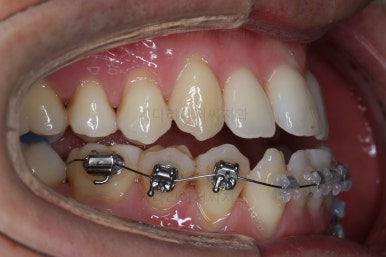

장치를 처음 부착했을 때의 입안 모습입니다.

아랫니가 해야될 작업이 많고 기간이 오래 걸리기 때문에 윗니는 최대한 늦게 장치를 부착하여 불편감을 최소화 하기로 했어요.

이번에 사용한 장치는 자가결찰 세라믹장치입니다. Empower clear(엠파워 클리어)라는 장치이고 흔히 많이들 알고계신 클리피씨와 동일한 유형의 장치에요.

클리피씨, 엠파워 등은 제품 이름일 뿐이죠. 클리피씨는 일본회사 장치, 엠파워는 미국회사 장치에요. 부산비수술교정 키다리아저씨치관느 여러 가지 이유로 엠파워 장치를 클리피씨보다 더 선호해요.

이 뽑은 자리로 앞니를 쭈욱 밀어넣으며 비대칭도 맞춰주기 위해서 미니스크류(마이크로 임플란트)라고 불리는 작은 나사를 잇몸뼈에 식립했어요.

이를 지지대로 삼아서 치아를 움직이게 됩니다.

아랫니를 계속 당겨주면서 가지런하게 하고 있어요.